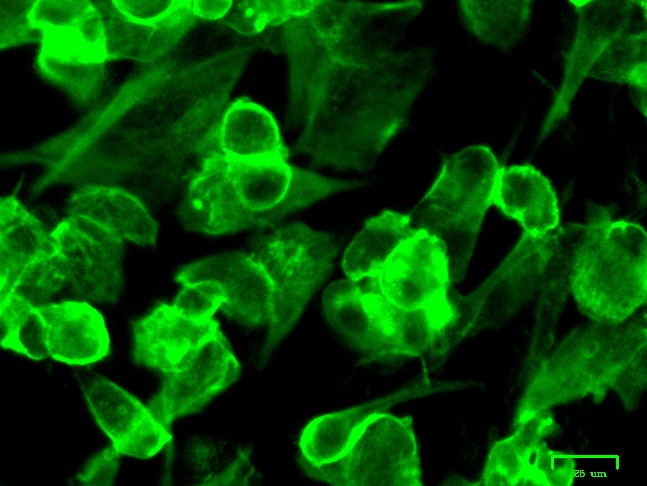

IN VITRO AND SILICO ANTIVIRAL SCREENING

In vitro and in silico evaluation of selected metabolites against Canine (CCoV) and Feline (FCoV) Coronaviruses.

MECHANISM OF ACTION

Investigating the therapeutic role of metabolites by mapping their interaction with host receptors (AhR/FPRs) and metal ions.